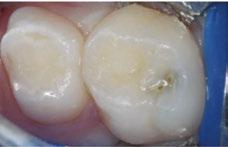

The 5-year-old patient featured in this case study did not benefit from early oral care and had multiple carious lesions. Considering the young age, high caries risk, and the uncertainty of compliance with follow-up appointments, I wanted to restore and seal all teeth in one visit. One quadrant is shown in this case study. The carious lesion on tooth J (65) was cavitated and prepared, restored, and sealed. Tooth I (64) was non-carious and would only be sealed (Figure 1).

surface of tooth I (64) was also lightly abraded with a diamond bur (Figure 2). The preparations were selectively etched with phosphoric acid, rinsed, and lightly dried (Figure 3). Bonding agent was applied to the entire occlusal surfaces of both teeth, air thinned, and light-cured (Figure 4).

Tooth J (65) was bulk-filled with Activa Kids. For this fast injection technique, I place the dispensing tip at the floor of the preparation and extrude the material without removing the tip until the preparation is completely filled (Figure 5). I like to do some minor manipulation of the filling material with hand instruments to create anatomy, as well as to ensure the material is flush with the surface of the preparation, and no air is trapped inside. Activa Kids is dual-cure, ideal for bulk filling, and can be cured with all lights. A thin topcoat of Activa Presto was placed as a sealant on the entire occlusal surface of teeth I and J (64 and 65) (Figure 6). Figure 7 shows the final clinical situation.

Figure 1 (left): Caries lesion on tooth J (65). Figure 2 (center): Preparation of tooth J (65) and abraded occlusal surface of tooth I (64). Figure 3 (right): Selective etch of enamel Figure 4 (left): Bonding agent is applied to both teeth I and J (64 and 65). Figure 5 (right): The preparation is filled with ACTIVA Kids Figure 6 (left): A thin topcoat of ACTIVA Presto is applied to the occlusal surfaces of teeth I and J (64, 65). Figure 7 (right): Final result